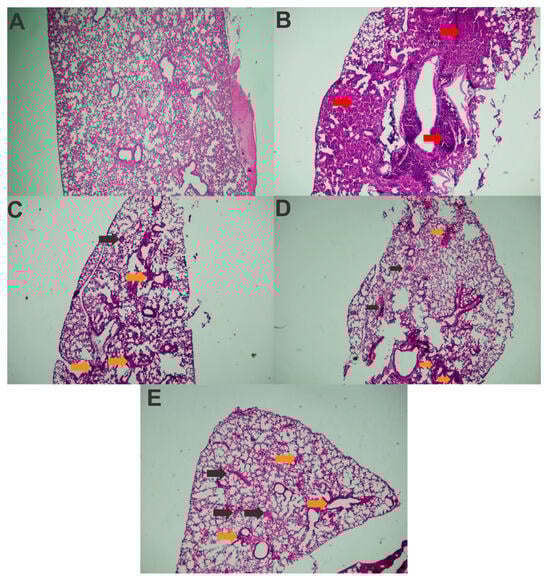

3.5. Immunization with rFimA and rMrkA Reduces Lung Colonization by K. pneumoniae

| Healthy Control | Challenged Control | FimA | MrkA | FimA + MrkA | |

|---|---|---|---|---|---|

| Polymorphonuclear Inflammatory Infiltrate | - | +++ | ++ | ++ | ++ |

| Mononuclear Inflammatory Infiltrate | - | ++ | ++ | + | ++ |

| Alveolar Structure Loss | - | ++ | + | + | ++ |

| Congestion | - | +++ | ++ | ++ | ++ |

| Edema | - | + | + | + | + |

| Pulmonary hemorrhage | - | +++ | ++ | ++ | ++ |